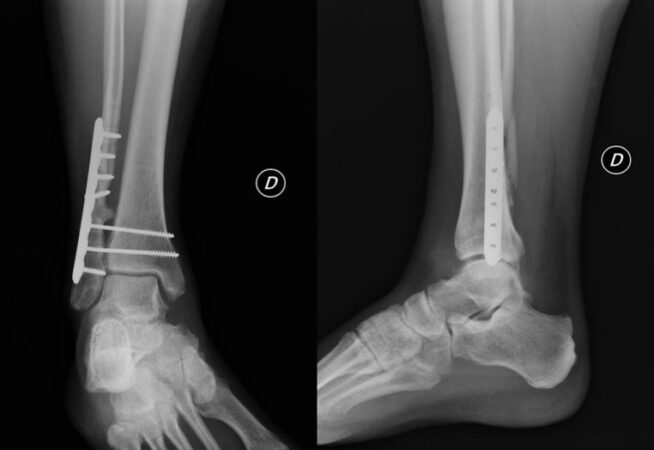

Consulte a un médico si tiene síntomas de una fractura, especialmente después de una lesión traumática. Su médico lo examinará físicamente en busca de signos y puede ordenar una radiografía.

Para las fracturas que necesitan una imagen más precisa, el médico puede ordenar una tomografía computarizada para ver qué tan grave es la lesión.

Reducción abierta

El médico hace la cirugía invasiva en los huesos que pueden haber roto en más de dos lugares.